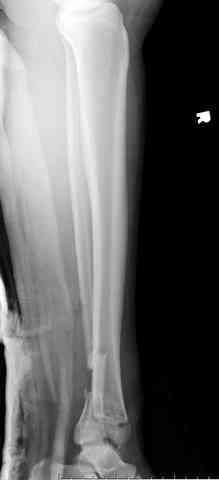

Яков изложил все необходимые аспекты лечения переломов пилона, и, не желая менять тему, решил выставить нашу точку зрения в двух клинических примерах.

При лечении внутрисуставных переломов типа "Pilon"

или "Tibial Plateau" на голени, применение простых

наружных фиксаторов типа "Spanning ExFix" или "Travelling ExFix" стал одним из стандартом этапного лечения.

Здесь выставлена пара случаев перелома пилона, оба

случая леченные этапным наружным фиксатором.